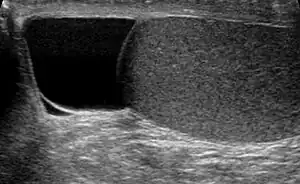

Ultrasound of a testicle (grey) and a spermatocele (black).